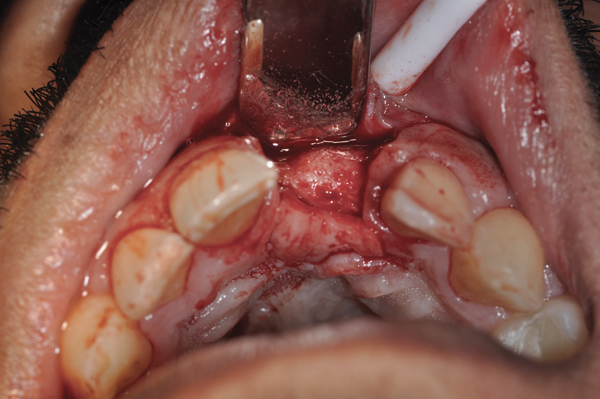

Fig 1. (Case 1) Tooth No. 19 manifested a buccal fistulous tract. Probing depth on the buccal was 8 mm.

Figure 1

Fig 2. Buccal flap elevated exposing buccal plate defect.

Figure 2